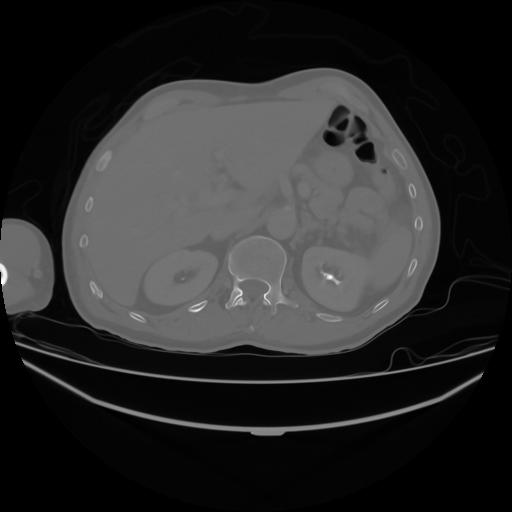

4 CUERPO,CE,Axial,3.0,CUERPO,,